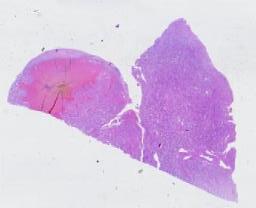

临床资料: 体检发现右肾占位1周余

大体所见: (右肾肿物)灰红不规则组织一块,大小3.3*2.5*2.2cm,表面灰红较光滑,局部突出一卵圆形肿物,大小约1.5*1.3*1.2cm,切面灰红灰黄灰黑,质中,无包膜,与周围组织界尚清,肉眼似累及肾被膜,肿物距剥离面最近处1cm,剥离面墨汁涂墨。余肾组织灰红,质中。